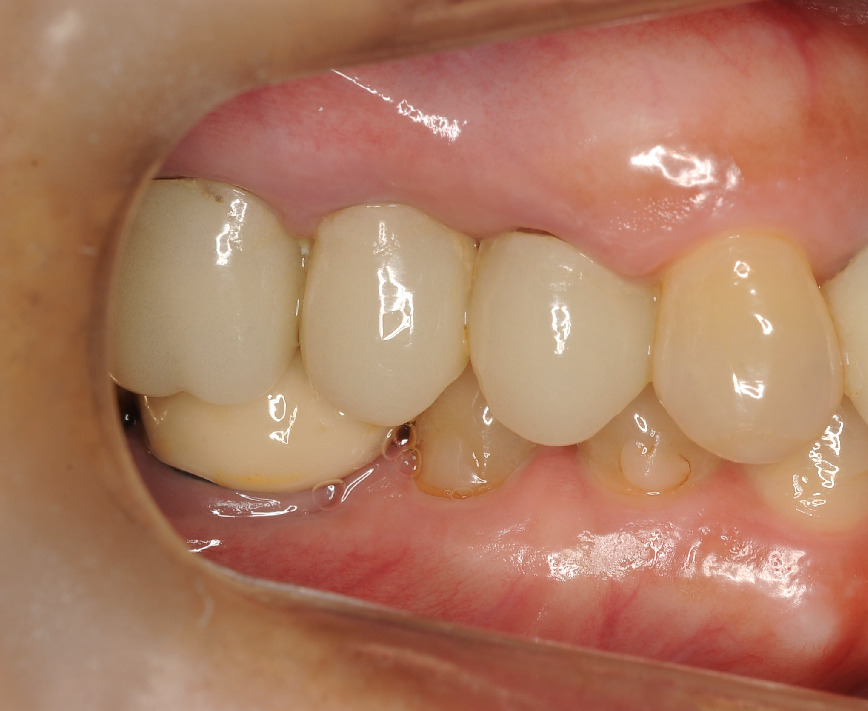

そして1年後

まだ、仮歯の状態ですが

骨の再生が見られます!

歯の揺れも落ち着きました。歯周ポケットも3mmまで回復。

患者さまと一緒に喜びました。有難いです!